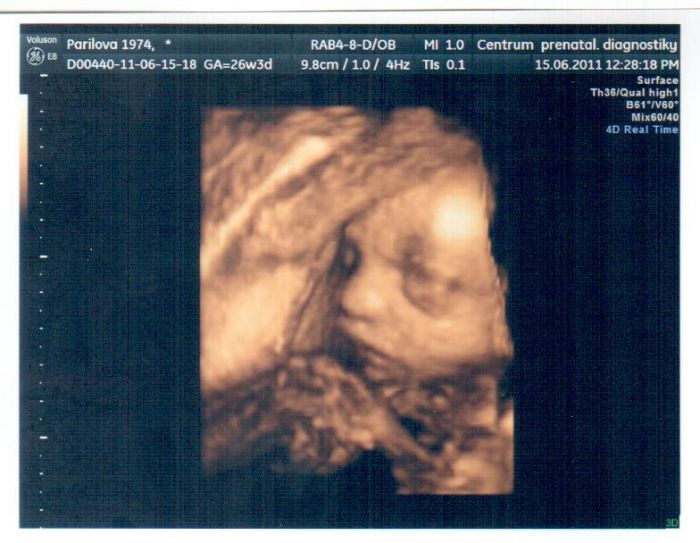

tak já dneska byla na kontrole i na fotečce 3D. fotečka už je v rámečku a čeká na stole na tatínka. Je to super, až ji oskenujem, tak vám ji sem dám. Na kontrole ještě neměla výsledky cukru, tak říkala že pokud zítra nezavolá tak jsou v pořádku. Tak ještě musím čekat do zítřka. Jinak mi bylo řečeno že je vše v pořádku - čípek, placenta, voda a amalej že velikostí odpovídá. Tak jsem spokojená. Na bolesti zad mi řekla at doma cvičím na balonu, že to by mělo aspon trochu pomoct.

Holky ten screening ve 30 tt já už budu mít u té mé dr. Aspoň mi to říkala, že to už na Veveří nepůjdu, že to udělá sama. Jsem se právě na to ptala v souvislosti s tou fotkou, že bych si ji nechala udělat až tam pudu znova. No a to mi na to odpověděla. Takže já se na tu Veveří na tu fotku objednávala zvlášť, moje má jen normální ult a ten asi bude v tom 30 stačit. Dneska mi tu fotku dělal Vlašín, stála 200,- a zrovna u toho i kontoroloval mozek, srdíčko a měřil ho. Sice mi k tomu nic přesnýho neříkal, jen že odpovídá 27tt a že váží necelé kilo. Jsem se ptala i na tu pusinku, že na této fotce má ten ret taky nějak dopředu a minule to máme taky tak a on se zasmál a prej, že se nemusím bát, že bych měla zajíčka. Tak jsem teda v klidu.

Jo a ta fotka se dělá prej jen nějak do 28tt, že pak už to prej není pěkné. Ji tatínek před chvilkou skenoval a zrovna ji rozeslal kde komu

Pavlo je moc pěkný, to má větší rtíky, což je u kluků pěkný

Pavli, já jdu na ten ultrazvuk ve 30. týdnu taky jen k mému doktorovi, říkal, že na Veveří jezdit už nemusíme. Jinak máš krásnou fotečku!